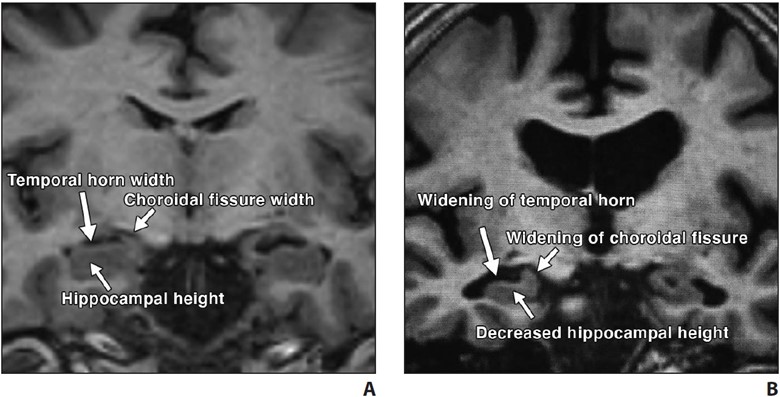

In typical AD, there is involvement of the medial temporal lobe and lateral temporoparietal cortex, precuneus, and lateral frontal lobe, which is manifested by loss of volume and hypometabolism [16]. The Scheltens scale is widely used for visual rating of hippocampal volume loss [17] (Fig. 2).

Fig. 2—Visual assessment of hippocampal atrophy performed using Scheltens scale.

A and B, Coronal T1-weighted MR images of view through hippocampus in patient with normal hippocampus (A) and in patient with mild hippocampal atrophy (B). Visual determination of hippocampal atrophy requires assessment of height of hippocampus, width of choroidal fissure, and width of temporal horn. Note near absence of CSF around hippocampus in patient with normal hippocampus (A) versus decreased hippocampal height and increased width of choroidal fissure and temporal horn in patient with mild hippocampal atrophy (B).